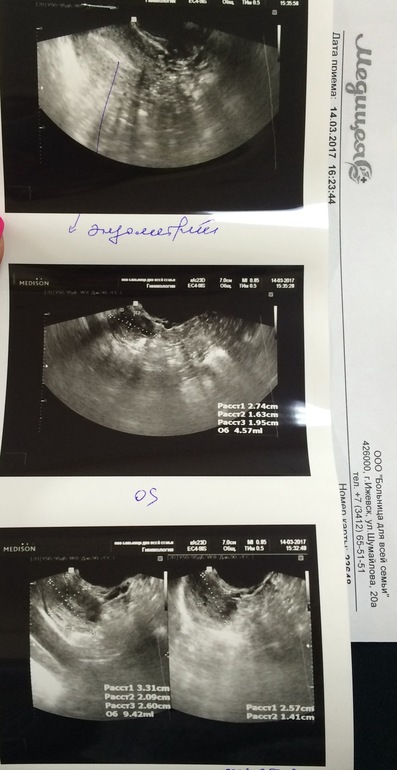

Девчата ,а вот и я с результатами узи!!немного в шоке )))в прошлый цикл через 5 дней после овуляции жт уже почти не видно было и эндик уменьшился .Сейчас я ходила не к своей узистке в другую больницу (но она не из дешёвых ).В общем эндик 10 -11 (сразу после овули он был 11) и жт 25!!(а было 20-21 после овуляции )Сегодня 8 дпо и что думаете на этот счёт?все-таки шанс есть??